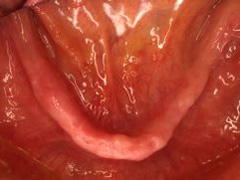

両側5歯症例両側5歯症例両側5歯症例 主訴-義歯のバネが壊れて手前の歯が痛んできた。 術前(旧義歯装着、鏡像) 術前(下顎粘膜面、鏡像)術前(下顎粘膜面、鏡像)術前(下顎粘膜面、鏡像) 術前レントゲン術前レントゲン術前レントゲン 術前口腔内(正面観)術前口腔内(正面観)術前口腔内(正面観)